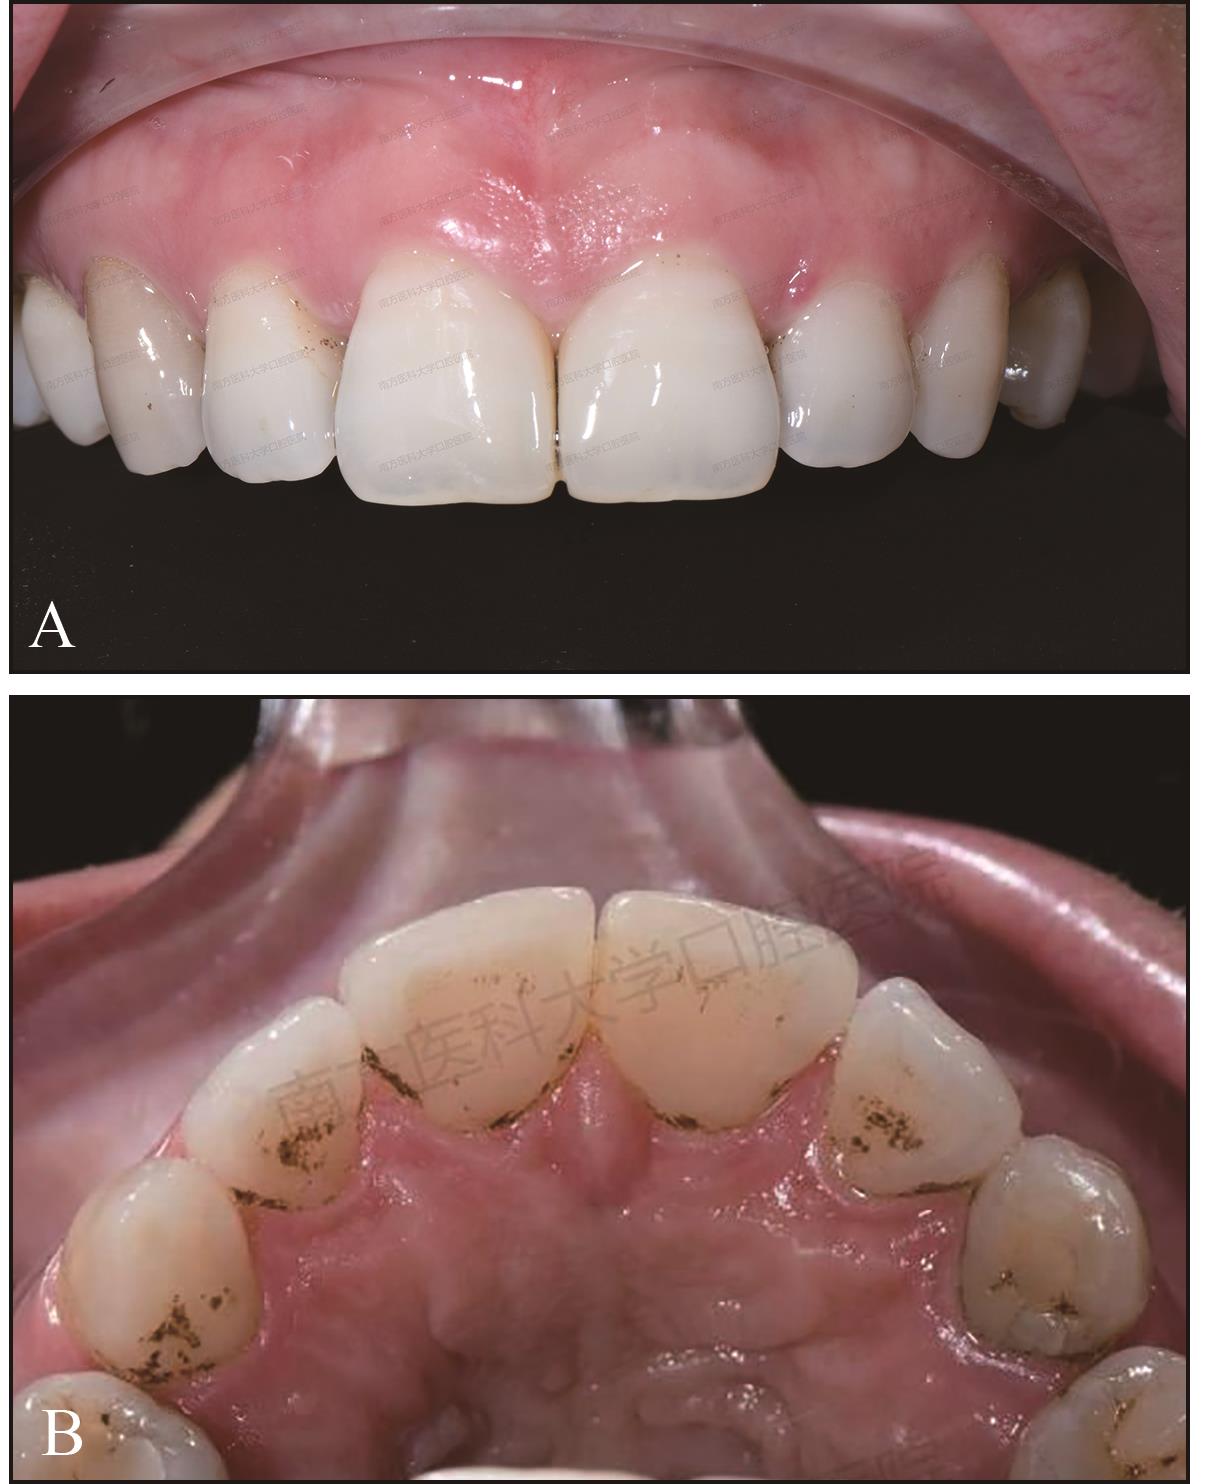

图 2

术前上前牙正面观"

图 5

术中去除成型片即刻的效果A:正面像;B:腭面像;C:牙科显微镜下唇、腭面像。"